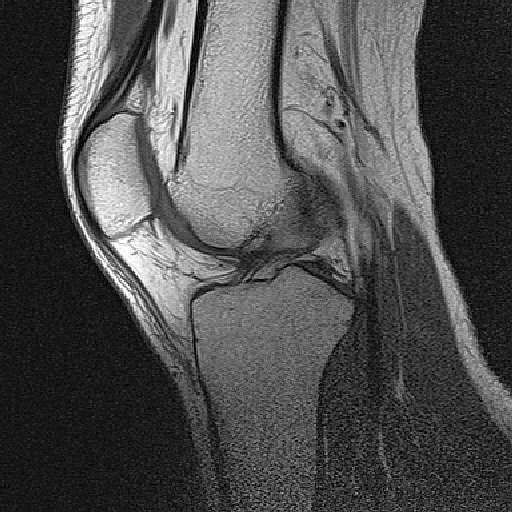

昨日は病院にMRIを撮りにいったんだった。

で、画像をCD-Rに焼かれたのを頂いて帰ったわけです。

まぁ、こんな感じ。

まぁ、医者じゃねーから分からんけど。

あ、俺のひざには愉快な奴が居るわ。

00000015.jpg